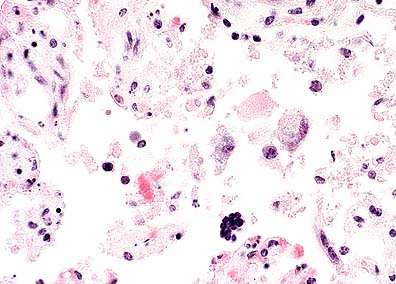

Perifollicular histiocytic inflammation with "sheep pox cells" - histiocyte-like cells with large vacuolated nuclei and eosinophilic intranuclear inclusions in a steer with lumpy skin disease. (HE, 200X, 53K)

Higher magnification of the above field. (HE, 400X, 50K).

Grossly, the skin lesions appear as variably sized, marked, firm swellings. With time, the centers of some of the swellings will become necrotic and ulcerated, resulting in a characteristic lesion known as a "sitfast." Histologically, the skin lesions are very distinct and share features in common with the other capripoxviruses, i.e. sheep pox and goat pox. There is often a striking paucity of epidermal changes. The dermis is edematous, cellular, and occasionally infarcted. Scattered throughout the inflammation are variable numbers of "sheep pox cells" - histiocyte-like cells with large vacuolated nuclei and poorly-defined eosinophilic cytoplasmic inclusions. In addition to skin, these "sheep pox cells" may be seen in other tissues altered by the virus such as nasal turbinates, trachea, and lung.

Subcutaneous or intradermal inoculation of LSD virus results in the development of localized swelling at the site of inoculation after four to seven days and enlargement of the regional lymph nodes. Generally, eruption of skin nodules occurs 7 to 19 days post-inoculation. Viremia occurs after an initial febrile period and persists for about four days. A variety of cell types, including epithelial and endothelial cells, pericytes and fibroblasts are infected by the virus. Vasculitis can result from viral infection of endothelium, pericytes and probably other cells in blood and lymph vessels. Infarction may occur in severe infections. LSD virus is present in skin nodules, normal appearing skin, lymph nodes, liver, kidneys, skeletal muscle, saliva, and semen of infected animals.